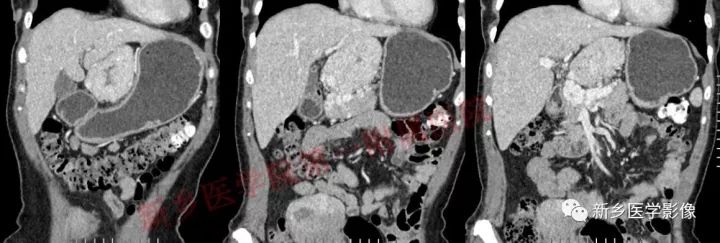

患者,女,47岁,发现“腹部肿瘤”半年,无明显不适。

肝胃间胰腺前上方见类圆形肿块,边界较清,大小约8.2cm×4.6cm×5.9cm,密度欠均匀,内见点状钙化,增强呈不均匀明显强化,内见片状低密度灶无强化区,其下部与相邻胰腺分界不清,周围见粗大回流血管影回流至门静脉,病变左侧及腹膜后、胃壁小弯侧见数个卵圆形稍大淋巴结及结节影,部分呈环形强化。

石蜡:(腹腔肿物、腹腔动脉旁、胰腺上缘)Castleman病(巨淋巴结增生),玻璃样变血管型。